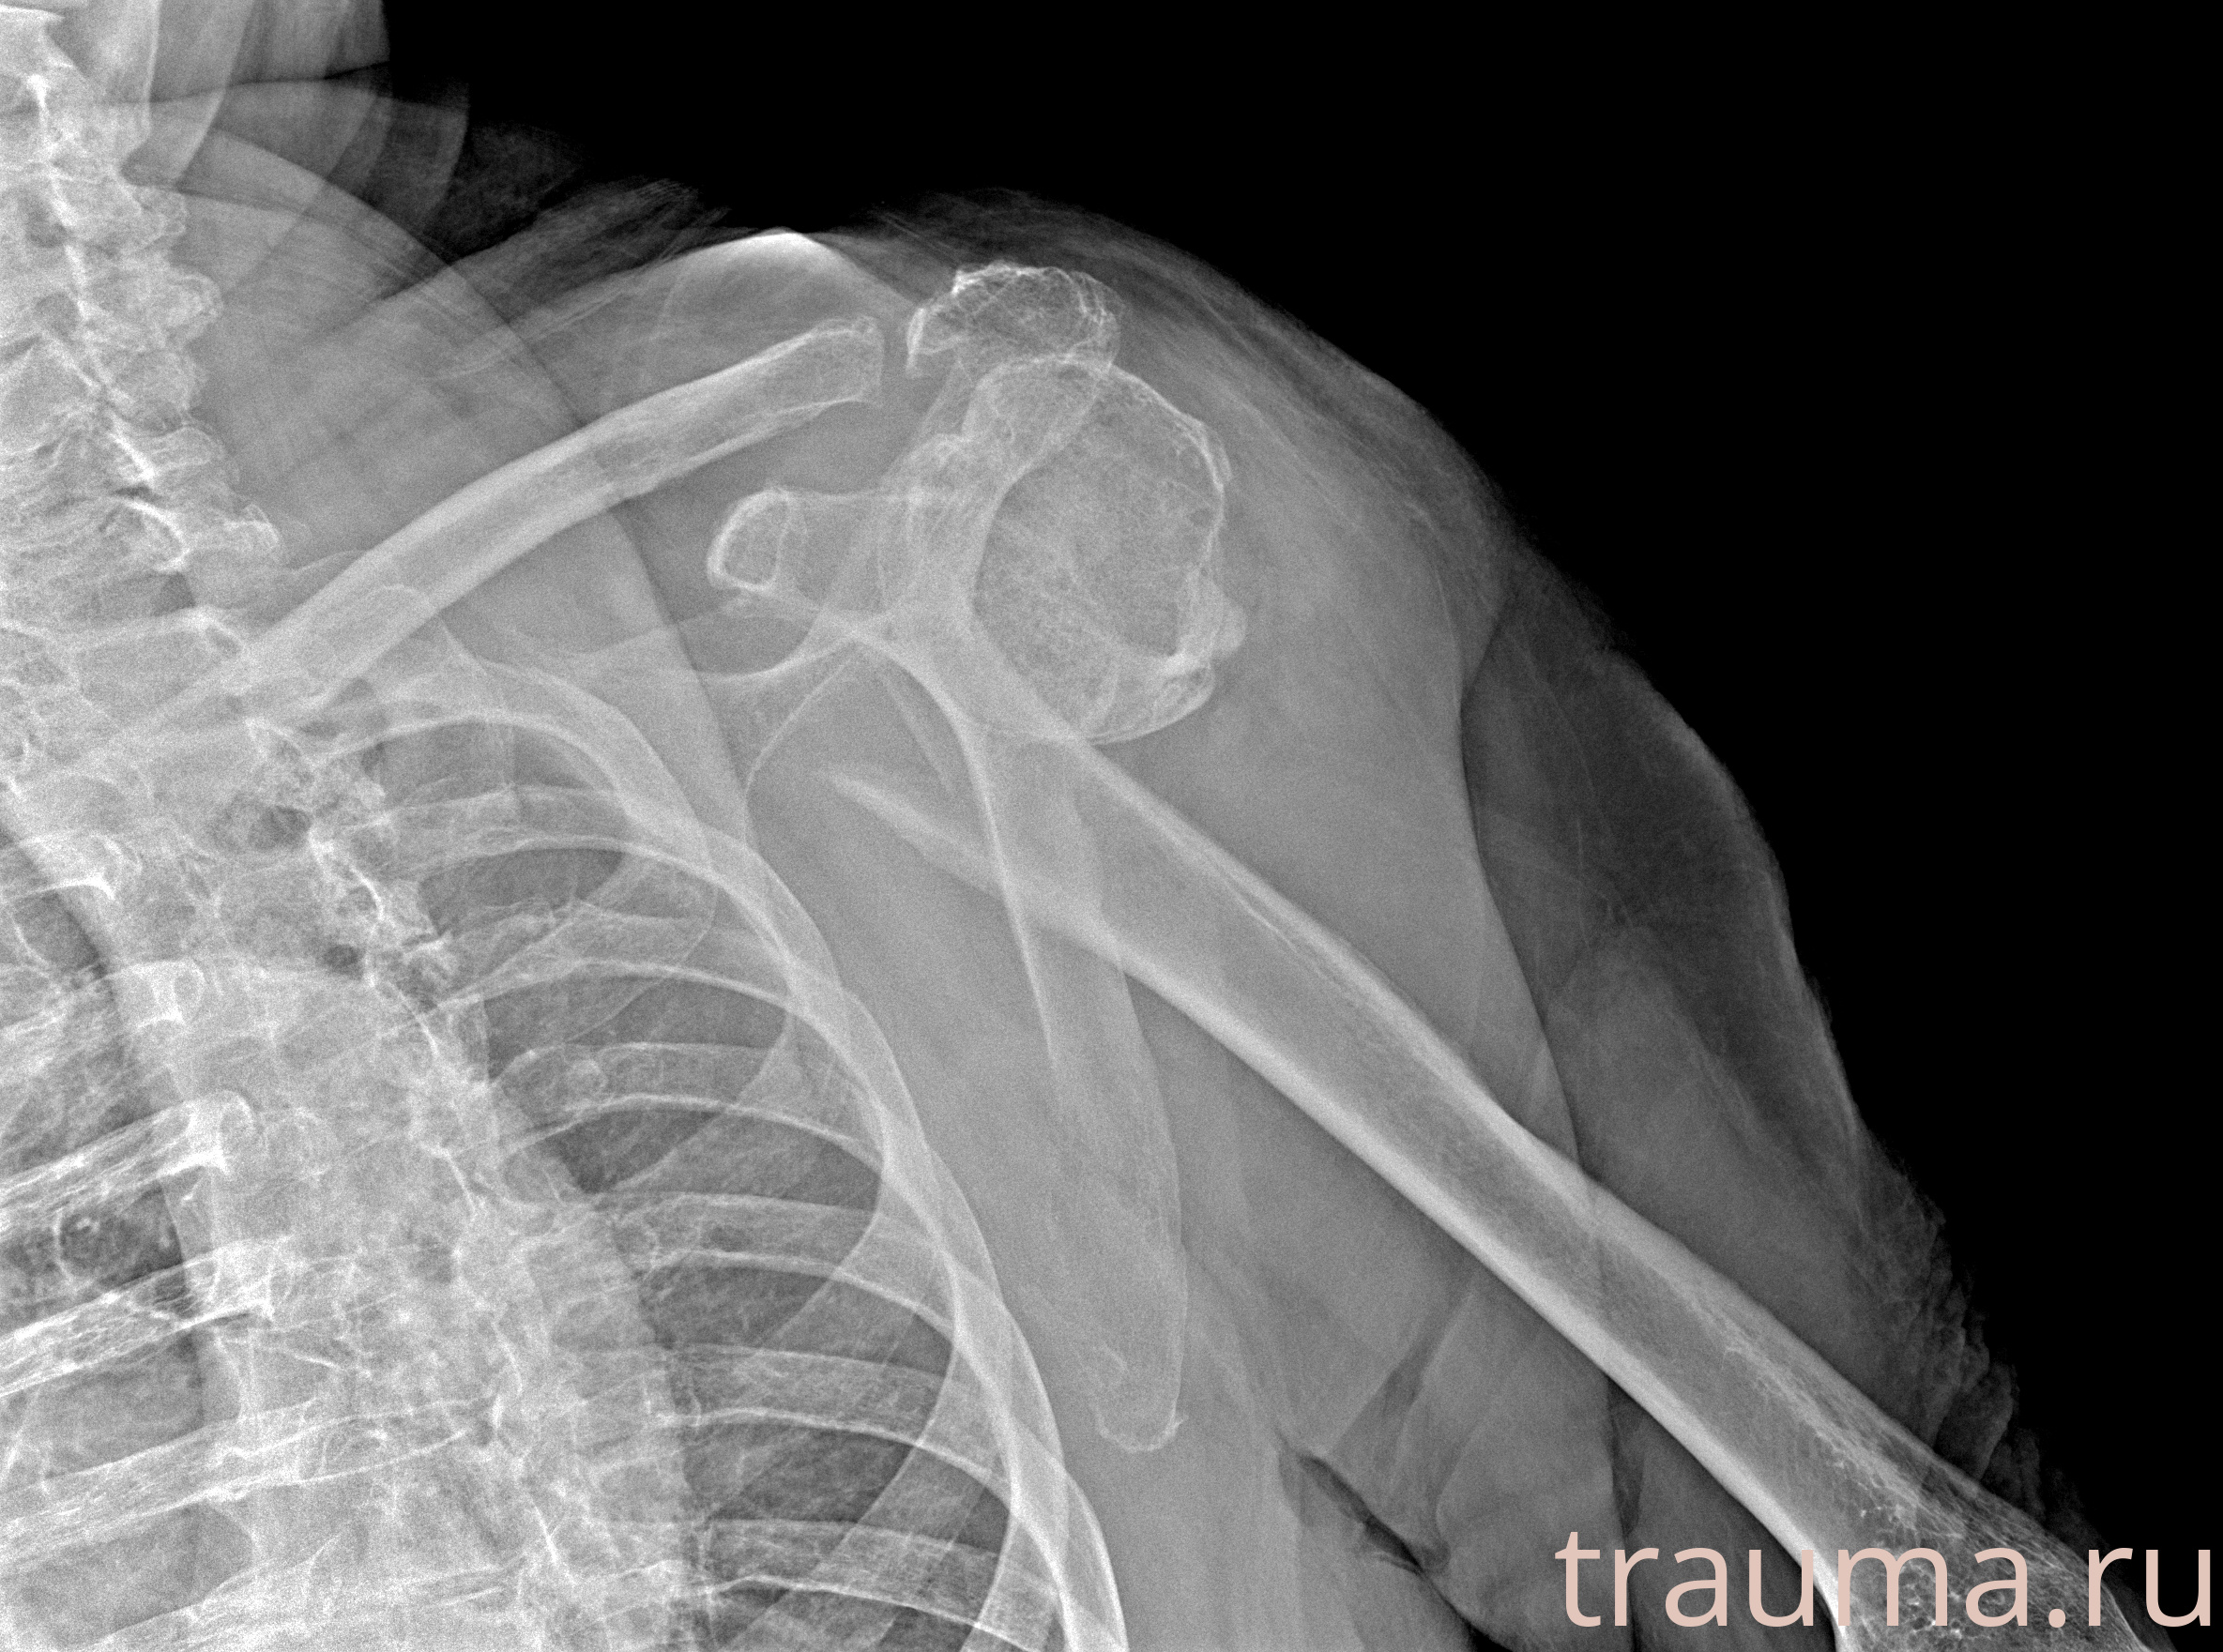

Рентген на дому: по вашему адресу приезжает врач-рентгенолог, травматолог-ортопед с мобильным рентгеновским аппаратом, проводит диагностику травмы или заболевания, делает необходимые рентгенограммы, дает рекомендации по дальнейшему лечению. Получить качественные снимки в домашних условиях возможно благодаря уникальной методике, разработанной МосРентген Центром для института  Склифосовского